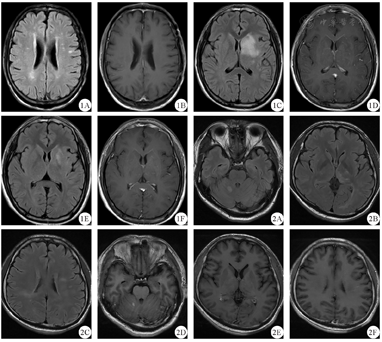

1A:病例1双侧放射冠及半卵圆中心FLAIR序列呈高信号,1B:病例1增强扫描后未见异常强化灶,1C:病例2左侧基底节区-放射冠-半卵圆中心FLAIR序列呈高信号,1D:例2软脑膜异常强化,1E:病例2 1个月后复查示病灶较前明显缩小,1F:病例2 1个月后复查示软脑膜异常强化减弱消失;2A~2C:病例3右侧小脑半球、双侧丘脑及双侧放射冠-半卵圆中心FLAIR序列呈高信号;2D~2F:病例3右侧小脑半球、双侧丘脑及双侧放射冠-半卵圆中心增强扫描后呈散在斑点状强化;FLAIR:液体衰减反转恢复

病例1 男性,51岁,因"反应迟钝伴幻觉2个月余"于2017年11月2日入院。体检:神志清晰,言语流利,反应迟钝,近期、远期记忆力下降,计算力减退,判断力、定向力正常,双眼视力下降,双侧瞳孔等大等圆、直径3 mm,直接及间接对光反射正常,余颅神经检查未见异常,四肢肌张力正常,肌力5级,共济运动检查未见异常,全身感觉系统检查未见异常,Romberg征(-),四肢腱反射正常,双侧病理征(-)。颈软,无抵抗。患者4个月前有双眼视力下降,当地医院考虑为视神经炎,予激素治疗,双眼视力逐渐恢复,遗留左眼视物不清。外院未行血清及脑脊液抗NMDAR抗体、MOG抗体、水通道蛋白4(aquaporin 4,AQP4)抗体、寡克隆区带检查。患者家族史、个人史无特殊,简易智力状态检查量表(MMSE)评分22分(初中学历)。腰穿脑脊液压力150 mmH2O(1 mmH2O=98 Pa),有核细胞数8×106/L,淋巴细胞为主,生化正常,血及脑脊液寡克隆区带、AQP4抗体均阴性,血清抗MOG-IgG阳性(1∶10),脑脊液抗MOG-IgG阴性,血清抗NMDAR抗体阳性(1∶100),脑脊液抗NMDAR抗体阳性(1∶10)。视诱发电位示双侧潜伏期延长,头颅MRI+增强扫描示双侧大脑半球皮层下白质内、双侧放射冠及半卵圆中心脱髓鞘病灶,增强未见异常强化(图1A、图1B)。全脊柱MRI+增强扫描未见明显异常。考虑诊断:MOG抗体病合并抗NMDAR脑炎重叠综合征。给予静脉滴注甲泼尼龙1000 mg 3 d,继而500 mg、240 mg、120 mg各3 d,然后改为口服泼尼松60 mg/d并逐渐减量,总疗程为半年。出院半年后电话随访,患者无幻觉、反应良好,遗留左侧视物稍欠清。

病例2 男性,16岁,因"头痛半个月,发热、右手无力、言语不能1周"于2020年3月13日入院。体检:神志清晰,言语欠流利,高级认知功能检查未见明显异常,12对颅神经检查未见明显异常,四肢肌张力正常,右侧肢体肌力4级,余肢体肌力5级,共济运动检查稳准,全身感觉系统检查未见异常,正常步态,四肢腱反射正常,双侧病理征(-)。颈软,无抵抗。患者既往史、家族史、个人史无特殊。腰穿脑脊液压力>330 mmH2O,有核细胞数94×106/L,生化正常,血及脑脊液寡克隆区带、AQP4抗体均阴性,血清及脑脊液抗MOG-IgG均阳性(1∶100),血清抗NMDAR抗体阴性,脑脊液抗NMDAR抗体阳性(1∶32)。视诱发电位示双侧潜伏期延长。头颅MRI+增强扫描示左侧基底节区-放射冠-半卵圆中心异常信号影,伴软脑膜异常强化,相应局部皮层稍肿胀(图1C、图1D)。全脊柱MRI+增强扫描未见明显异常。考虑诊断:MOG抗体病合并抗NMDAR脑炎重叠综合征。给予静脉注射丙种球蛋白400 mg/(kg·d) 5 d联合静脉滴注甲泼尼龙(1000 mg 5 d,500 mg 3 d,240 mg 2 d,120 mg 1 d),后改为口服泼尼松60 mg/d并逐渐减量,预计总疗程半年。2020年3月28日时患者言语流利,无头痛,右手无力出院。1个月后复查腰穿脑脊液压力225 mmH2O,有核细胞数8×106/L,头颅MRI+增强扫描可见病灶较前明显缩小(图1E、图1F),血及脑脊液寡克隆区带、AQP4抗体均阴性,血清抗MOG-IgG阳性(1∶1000),脑脊液抗MOG-IgG阳性(1∶32),血清及脑脊液抗NMDAR抗体均阴性。复诊时,患者未诉头痛、肢体无力等不适,予继续随访患者症状及病灶变化情况。

病例3 男性,37岁,因"记忆力下降20 d,加重伴视力下降2 d"于2019年12月5日入院。体检:神志清,精神可,近期、远期记忆力下降,计算力减退,判断力、定向力减退,双耳听力粗测下降,视物模糊,余颅神经检查未见异常,四肢肌张力正常,肌力5级,共济运动检查未见异常,全身感觉系统检查未见异常,Romberg征(-),四肢腱反射正常,双侧病理征(-)。颈软,无抵抗。患者既往史、家族史、个人史无特殊,MMSE量表评分19分(小学学历)。腰穿脑脊液压力155 mmH2O,有核细胞数16×106/L,淋巴细胞为主,生化正常,血及脑脊液寡克隆区带、AQP4抗体均阴性,血清抗MOG-IgG阳性(1∶10),脑脊液抗MOG-IgG阴性,血清抗NMDAR抗体阴性,脑脊液抗NMDAR抗体阳性(1∶32)。视诱发电位示左侧潜伏期延长,右侧正常。头颅MRI+增强扫描示右侧小脑半球、双侧丘脑及双侧半卵圆中心多发病灶,考虑脱髓鞘病变可能性,散在斑点状强化(图2)。考虑诊断:MOG抗体病合并抗NMDAR脑炎重叠综合征。给予静滴地塞米松磷酸钠10 mg/d,2 d后患者精神较亢奋,理解力较前下降,出现幻觉,遂改为静脉滴注甲泼尼龙1000 mg/d加用奥氮平2.5 mg/d。当甲泼尼龙1000 mg静滴5 d后减至500 mg静滴时,患者自觉视物不清较前加重,不配合治疗出院。出院后半年电话随访,患者仍有视物模糊,存在被害妄想,预后欠佳。